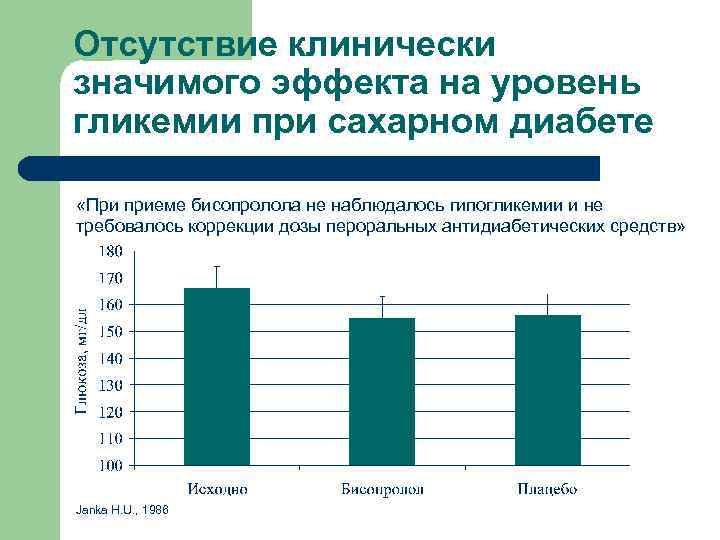

Отсутствие клинически значимого эффекта на уровень гликемии при сахарном диабете «При приеме бисопролола не наблюдалось гипогликемии и не требовалось коррекции дозы пероральных антидиабетических средств» Janka H. U. , 1986